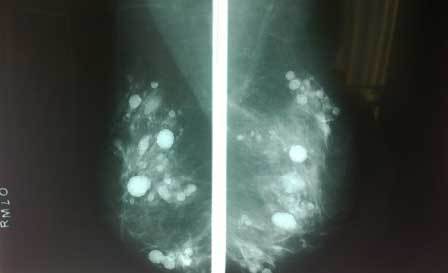

Nữ bệnh nhân 62 tuổi, nhập viện trong tình trạng đau nhức bầu ngực, kết quả nhũ ảnh ghi nhận hàng trăm khối cản quang và không thể phân biệt silicon và khối u. Để tránh hiểm họa khôn lường, bác sĩ đã buộc phải đoạn cả 2 vú của người bệnh.

Hình ảnh kiểm tra không phân biệt được khối u và khối silicon nằm dày đặc trong bầu vú |

Các bác sĩ đã tiến hành siêu âm, nhũ ảnh nhưng không thể phân biệt được khối u và hàng trăm khối silicon lỏng trong 2 bầu vú của người bệnh. “Bà T. rất hoang mang và lo lắng trước nguy cơ bị ung thư vú. Theo khuyến cáo của y văn thế giới, những trường hợp như bệnh nhân T. nếu phẫu thuật chẳng những sẽ rất khó có thể lấy hết được các khối silicon mà còn khiến bầu vú của người bệnh bị biến dạng. Bệnh nhân đã chấp nhận phương pháp đoạn nhũ, nạo hết toàn bộ mô vú để giải thoát khỏi những di chứng do các khối silicon gây ra. Sau phẫu thuật, sức khỏe người bệnh đã ổn định.